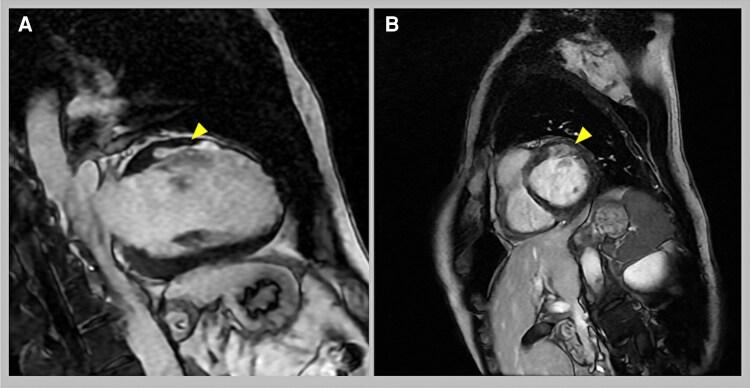

A 37-year-old man with a history of panic disorder was transported to our institute after he experienced hyperventilation during a panic attack and developed chest pain and a subsequent loss of consciousness. During transportation, ventricular fibrillation was observed on electrocardiography, and sinus rhythm was successfully restored with defibrillation. Suspecting hyperventilation-induced coronary vasospasm, a hyperventilation test was performed, which induced 90% coronary spasm accompanied by chest pain. An acetylcholine (ACh) provocation test revealed total occlusion of the left main bifurcation, with significant ischaemic ST-T elevation. Medication with a calcium channel blocker (nifedipine 40 mg per day), nitrate (isosorbide dinitrate 40 mg per day), and statin (rosuvastatin 20 mg per day) was initiated. Three months later, a repeat ACh provocation test performed to assess response to the medications revealed 90% stenosis with ischaemic ST-T changes and chest discomfort. Subsequently, a subcutaneous cardioverter defibrillator was implanted to address refractory vasospastic angina.

一名有惊恐障碍病史的37岁男性在惊恐发作期间经历过度通气并出现胸痛,随后失去意识,被送往我院。在转运过程中,心电图显示心室颤动,通过除颤成功恢复窦性心律。怀疑是过度通气诱发的冠状动脉痉挛,进行了过度通气试验,该试验诱发了90%的冠状动脉痉挛并伴有胸痛。乙酰胆碱(ACh)激发试验显示左主分叉完全闭塞,伴有明显的缺血性ST-T段抬高。开始使用钙通道阻滞剂(硝苯地平每日40毫克)、硝酸盐(硝酸异山梨酯每日40毫克)和他汀类药物(瑞舒伐他汀每日20毫克)治疗。三个月后,为评估药物反应而进行的重复ACh激发试验显示有90%的狭窄,伴有缺血性ST-T改变和胸部不适。随后,植入了皮下心脏复律除颤器以治疗难治性血管痉挛性心绞痛。